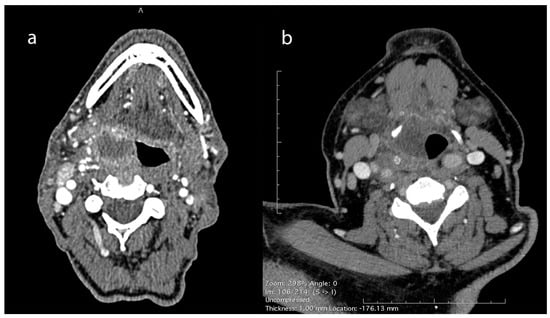

Table 3 tabulates the summary of patients with PMAs’ physical examination findings. One-sided lateral pharyngeal wall edema was invariable; pyriform sinus, vallecula, uvula, peritonsillar swelling, and unilaterally enlarged tonsil were noticed in 41%, 27%, 27%, 26%, and 18% of patients, respectively, while nasopharyngeal edema and adenoiditis were found in three patients (Figure 4). Tenderness during palpation of the larynx was noted in all patients. The most common laryngeal endoscopic finding was arytenoid edema (20%), whereas the glottic and subglottic areas were spared. Neck swelling was present in 25% of patients.

Lateral pharyngeal wall edema was a consistent endoscopic finding in all cases, while, in some of them, edema in other oropharyngeal parts coexisted. In 43 (41%) patients with abscess extension to the hypopharyngeal part of the PMA, edema was extended to the pyriform sinus, while in those where pus reached the most inferior part of the PMS, arytenoid or aryepiglottic fold edema coexisted. No other findings from laryngeal endoscopy were recorded, while follow-up of the five cases with epiglottic edema and the two cases with true vocal cord edema revealed the presence of epiglottic retention cysts and Reinke edema, respectively. Tenderness during palpation of the larynx (bilateral movement) was also a constant finding in all patients. Similar findings were reported by Skoulakis et al. [7].

Figure 4. Endoscopic findings in PMA cases. One-sided lateral pharyngeal wall edema (ac) and arytenoid edema (b) were the common findings during endoscopy.